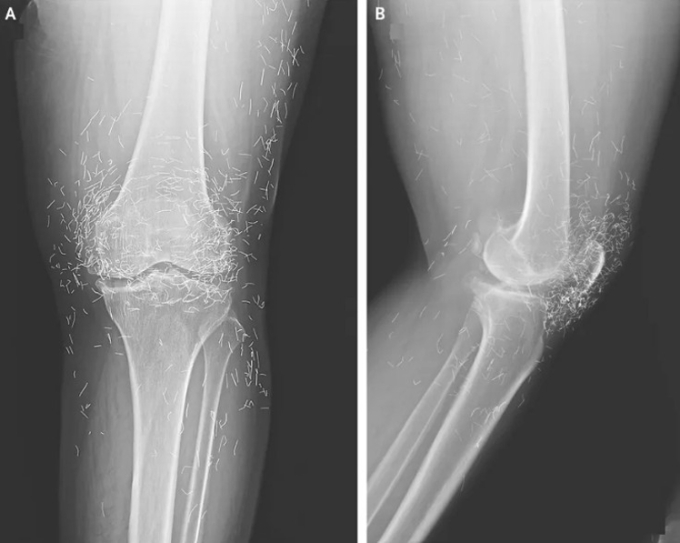

Hình ảnh X-quang mặt trước (A) và mặt bên (B) khớp gối trái của bệnh nhân cho thấy những đường mảnh xuất hiện trong hình chính là các sợi chỉ bằng vàng siêu nhỏ. Ảnh: The New England Journal of Medicine

Một phụ nữ 65 tuổi tại Hàn Quốc nhập viện trong tình trạng hai đầu gối đau nhức dữ dội dù đã điều trị qua nhiều phương pháp. Trước đó, bà bị thoái hóa khớp gối nhưng đã ngưng dùng thuốc Tây y do tác dụng phụ gây đau dạ dày. Bà dùng liệu pháp châm cứu với tần suất nhiều lần mỗi tuần.

Kết quả chụp X-quang khiến các bác sĩ kinh ngạc khi phát hiện hàng trăm đốm kim loại nhỏ bao vây kín khớp gối bệnh nhân. Đây là những đoạn chỉ vàng vô trùng được chủ ý để lại trong mô cơ trong quá trình châm cứu nhằm tạo kích thích giảm đau liên tục. Báo cáo không đề cập việc những sợi chỉ vàng có được lấy ra khỏi cơ thể bệnh nhân hay không nhưng trong các trường hợp trước đây, chúng thường được để nguyên tại chỗ. Tuy nhiên, việc không loại bỏ các sợi chỉ vàng vẫn tiềm ẩn rủi ro hình thành nang do các dị vật này gây ra.

Trong báo cáo về ca bệnh trên, các bác sĩ cho biết châm cứu bằng chỉ vàng vốn được sử dụng phổ biến tại châu Á để điều trị cả thoái hóa khớp và viêm khớp dạng thấp. Tuy nhiên, không có bằng chứng nào cho thấy phương pháp đó thực sự hiệu quả, thậm chí, một số trường hợp còn có thể gián tiếp làm bệnh trầm trọng hơn do khiến bệnh nhân lỡ mất cơ hội được điều trị đúng cách và kịp thời.

Ngoài ra, các sợi chỉ này có thể di trú bên trong cơ thể và những mảnh vụn của chúng có thể làm tổn thương mô lân cận. Chuyên gia y tế cảnh báo những sợi chỉ vàng được đưa vào cơ thể khi châm cứu có thể gây khó khăn cho việc đọc kết quả X-quang. Nhiều chuyên gia khác cũng cho rằng việc cấy chỉ vàng khiến bệnh nhân không thể chụp MRI (cộng hưởng từ) do nguy cơ kim loại bị dịch chuyển và làm tổn thương các động mạch.